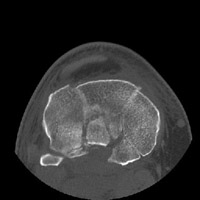

- Click on the image for a larger versionDAxial CT. This image through the tibial plateau demonstrates the extensive nature of the fracture involving both sides of the tibial plateau.